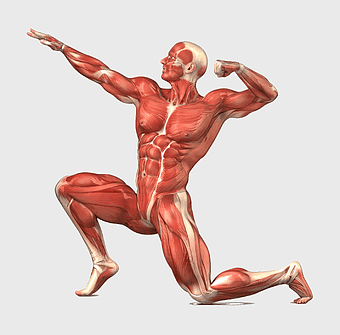

human anatomy diagram, muscular system illustration, human body muscles, fitness anatomy chart, skeletal muscle structure, human physiology study, muscle group analysis -

muscular system illustration, human anatomy diagram, fitness professional figure, skeletal muscle structure, muscular development, human body musculature, anatomical study -

human muscular system anatomy, fitness professional bodybuilder, human body organ systems, skeletal muscle tissue, full-body muscle diagram, anatomical muscle structure, human physiology illustration -

human muscular system illustration, muscle anatomy human body, fitness professional bodybuilder, human back and abdomen muscles, anatomical muscle structure, human skeletal muscle system, detailed human muscle chart -